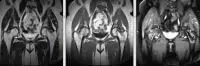

На МРТ-зображенні приклад множинного некрозу мозку кісток, що утворюють кульшові суглоби.